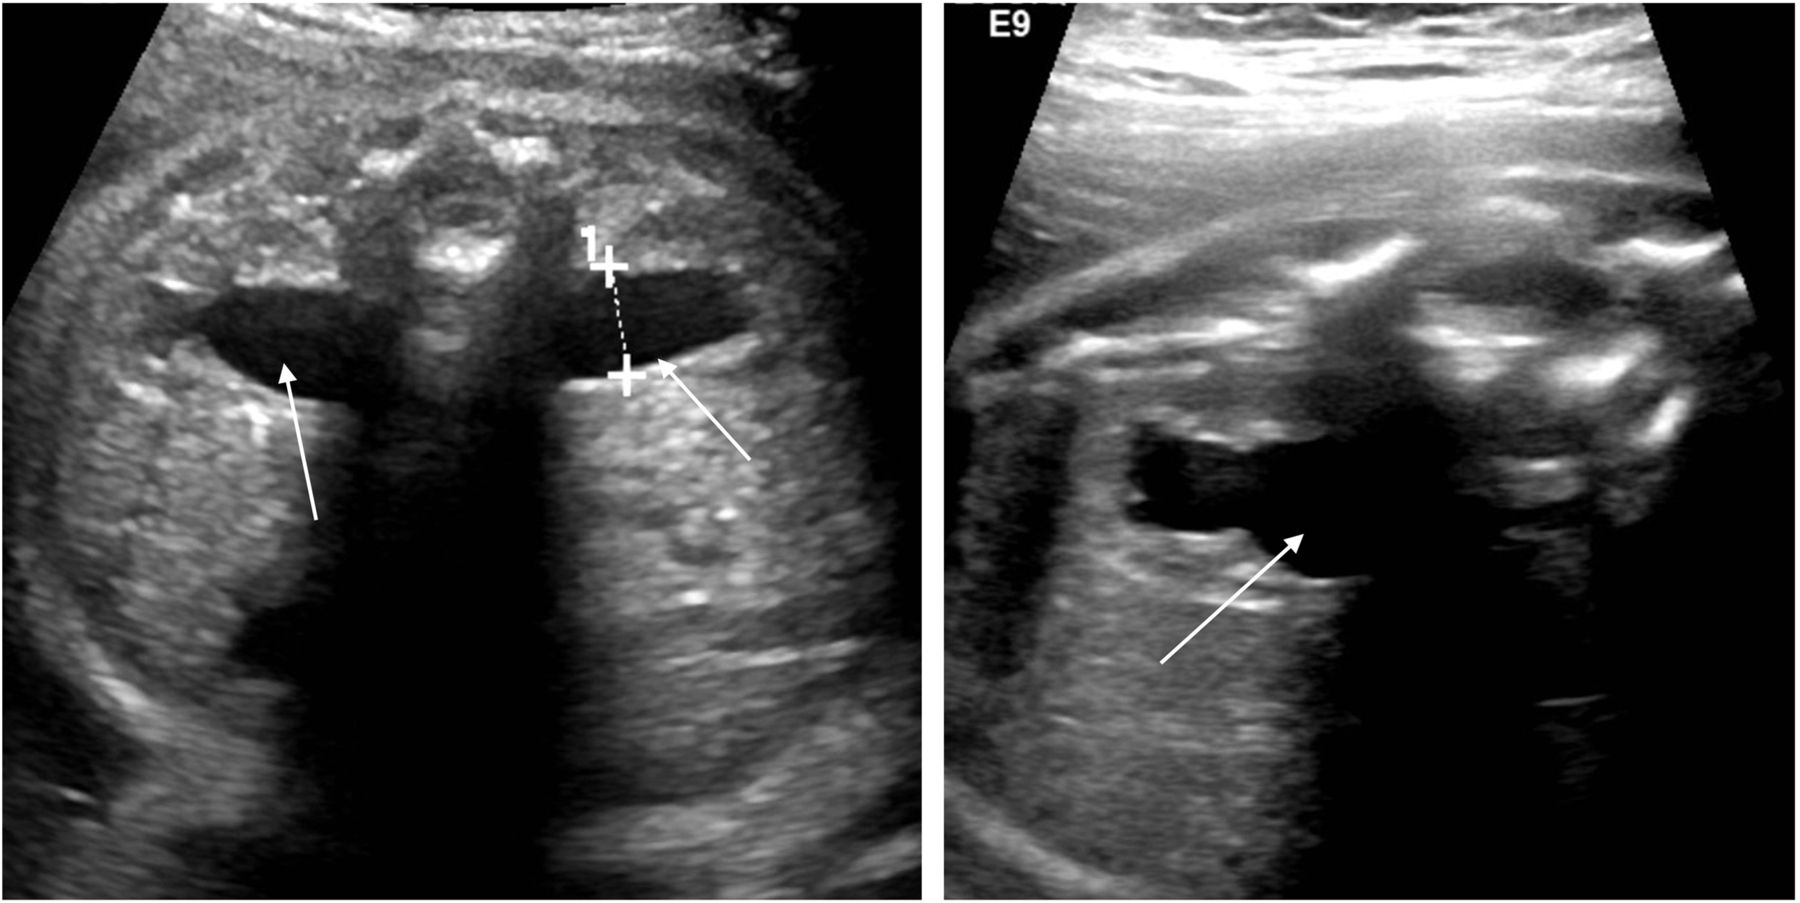

در سونوگرافی پزشک به موارد زیر توجه می کند:

- وجود هیدرونفروز در یک یا هر دو کلیه

- شدت هیدرونفروز

- اگر هیدرونفروز فقط در یک کلیه باشد یا شدت آن خفیف باشد نوزاد در یک هفتگی سونوگرافی می شود و بر اساس نتایج سونوگرافی پزشک برای اقدامات بعدی تصمیم گیری می کند. پزشک ممکن است آنتی بیوتیک جهت پیشگیری از عفونت کلیه ها تجویز کند.

- اگر هیدرونفروز در هر دو کلیه وجود داشته باشد و یا شدت آن شدید باشد نوزاد در روزهای اول تولد سونوگرافی می شود. پزشک آنتی بیوتیک جهت پیشگیری از عفونت کلیه تجویز می کند. همچنین پزشک ممکن است سایر تست های تشخیصی را درخواست کند.

سلام، در سونو غربالگری دوم مشخص شد جنین ورم خفیف ۵.۲ در کلیه چپ و ۵.۱ در کلیه راست داره، در سونو هفته ۲۶ ورمی در کلیه راست دیده نشد اما ورم کلیه چپ به ۱۳.۳ mm رسید. حجم مایع آمنیوتیک نرمال و ۱۳ cm است. دکتر دستور انجام سونو برای یک ماه دیگه را داده، میخواستم نظر پزشک محترم را بدونم که آیا انجام زایمان زودرس و جراحی نوزاد بعد از تولد در چنین حالتی، اجتناب ناپذیره؟

احتمالا جنین تنگی در ناحیه upj یعنی خروجی کلیه دارد یا با احتمال کمتر ریفلاکس مثانه به حالب دارد که با عددی که شما گفتید خفیف بوده و جای نگرانی ندارد خصوصا که اکثرا در طول بارداری بهتر میشوند. البته در موارد کمی شدت، بیشتر خواهد شد و تنها در این موارد نارد ممکن است نیاز به مداخله جراحی باشد.

دیامتر لنگچه کلیه راست ۱۲م م ضخامت کورتکس آن ۳ م م

ودیامترلنگچه چپ ۲۶ م م وضخامت کورتکس آن ۱م م